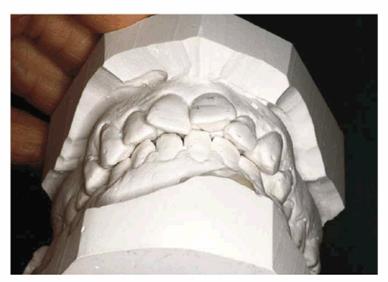

TREATMENT: Because of uncertainty about the ability to achieve a

satisfactory result using restorative treatment options to correct the

significant rotation of the lateral incisors, diagnostic casts were made. A

diagnostic wax-up was used to determine if appropriate modifications could be

made that would correct this crowding.

Using a diagnostic cast, it was noted that the space available (see Figures 24-4D, and 24-4E) for tooth #7 was 4.5 mm and for

tooth #10 was 6 mm. The central incisors were evaluated, and tooth #8 was found

to be 8.75 mm and tooth #9 was 8 mm. The crowding problem was then summarized

as the deficiency in arch space of 1.5 mm for tooth #7 with an excessive width

of 0.75 mm for tooth #8. If the distal of tooth #8 was reduced by 0.75 mm, then

the space needed to be created for tooth #7 was 0.75 mm if both sides of the

arch were to have a symmetric appearance.

Figure 24-4D: Diagnostic cast-facial view.

Figure 24-4E: Diagnostic cast-incisal view. By measuring the available arch space for each incisor, the source of the crowding problem was determined. The results of this analysis demonstrated a 1.5-mm deficiency in the area of tooth #7 and an excessive amount of arch space with tooth #8.